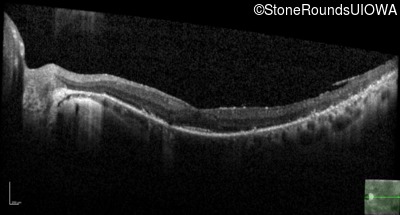

Optical Coherence Tomography - Left - 20/25 sc

Exemplar / OCT Stack

OCT Stack